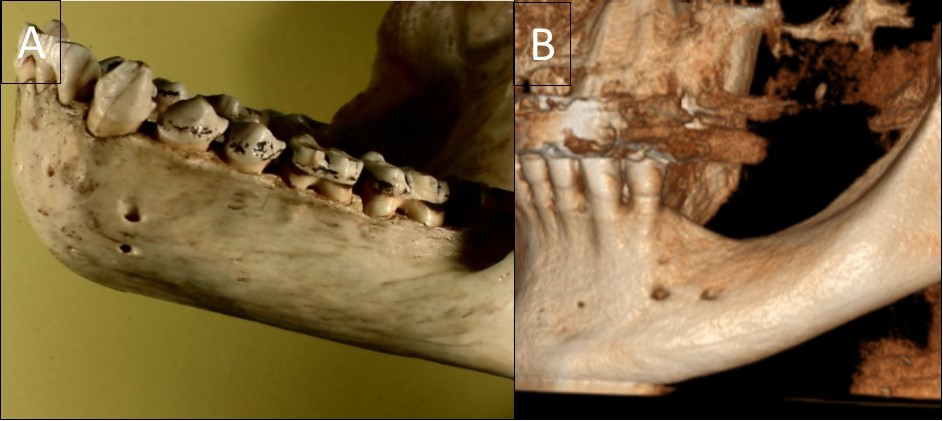

The typical images from modern human and great apes with different anatomical features were shown in Figure 1 and Figure 2. A group of variables were categorized as: the presence of the incisive canal, the number of mandibular canal bifurcations, the potential occurrence of an anterior loop, the presence of the incisive canals, its end-point and connection of the incisive to the lingual canals (Figure 3). Interspecific variability was determined by comparing contemporary human and great ape mandibles. In this analysis, mandibles from the different geographical locations were grouped in the human group, and then compared to mandibles of chimpanzees and gorillas.

Figure 2.A general view of a gorilla mandible with a vertical double foramen (A) and a human mandible with a horizontal double foramen (B).